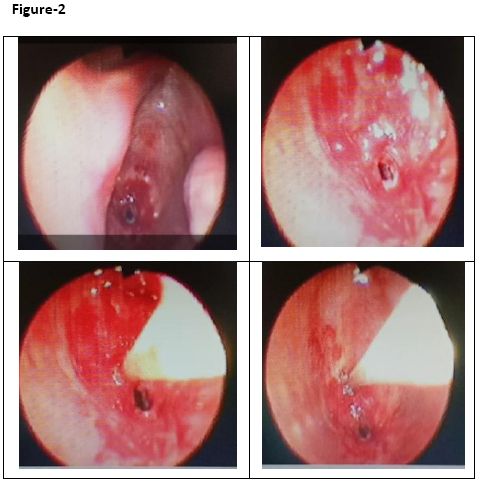

Contrast Enhanced Computed Tomography (CECT) examination of the neck was performed which revealed moderate focal subglottic tracheal stenosis 2.0 cm below the vocal cords with a transverse luminal diameter of less than 2.0 mm (Figure-1). The antero-posterior luminal diameter was 9 mm at the level of stenosis. Flexible fibreoptic bronchoscopy revealed normal vocal cords and subglottic tracheal stenosis with luminal opening of 1.5-1.8 mm with a thickened trachea around the small opening. Even, scope of 2.2 mm diameter could not be negotiated through small tracheal opening (Figure-2). Endotracheal biopsy was taken from around the thickened tracheal luminal opening which revealed fragments of stratified squamous epithelium revealing acanthosis, exocytosis and neutrophils showing mild to moderate reactive atypia.

Figure-2:  Subglottic stenosis 2 cm below the vocal cords with narrow tracheal lumen 1.8 mm in size.